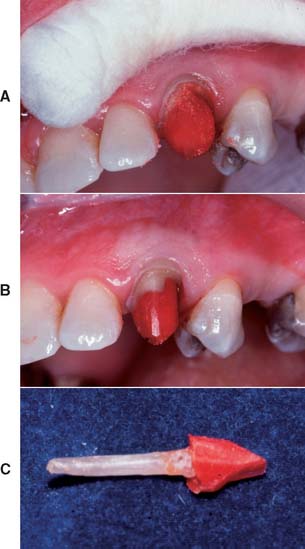

Amalgam cores are suitable for restoring posterior teeth, particularly when some coronal structure remains. The procedure described by Nayyar and associates,45 with amalgam also used for the posts, is conservative of tooth structure. The cores are placed during the same appointment as the root canal obturation, because then the teeth are still isolated by the rubber dam, the practitioner is still familiar with the root canal structure, and the cores can serve as a support for the interim restoration (Fig. 12-38).

Fig. 12-38 A to E, Retention for an amalgam core can be obtained from the root canal system, preserving as much tooth structure as possible.

(B to D, Courtesy Dr. M. Padilla.)

Mandibular premolars and molars with a reasonable amount of remaining coronal tooth structure, when coupled with a circumferential cervical band of tooth structure with restricted taper of about 2 mm, can often be restored with amalgam directly condensed into the chamber. Core buildups in molars with one or more missing cusps benefit from one or more cemented posts around which the amalgam can be condensed. The posts provide the additional retention, which was compromised because of the missing tooth structure. In mandibular molars, the larger distal canal is recommended for post placement. In maxillary molars, the palatal canal is used (see Fig. 12-2C and D).